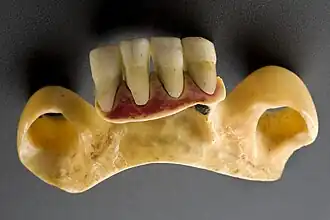

Um 450 v. Chr. wurde in Rom eine Kommission damit beauftragt, ein als Zwölftafelgesetz bekannt gewordenes Grundgesetz zu erstellen. Dort heißt es in der Tafel X, „man soll ‚dem Leichnam‘ kein Gold beigeben. Aber wer Zahnersatz auf der Basis von Golddrahtgebinde hat, mit dem fehlende Zähne durch menschliche oder tierische Zähne mit Golddraht oder Goldbändern an den benachbarten Zähnen befestigt sind,[69] den damit zu begraben oder zu verbrennen soll dagegen kein Vergehen sein“, woraus abzuleiten ist, dass damals Zahnersatz bereits weit verbreitet war.

In den Epigrammen Martials (40–102/104) ist ebenfalls von Zahnersatz die Rede: Sic dentata sibi videtur Aegle emptis ossibus indicoque cornu („So sieht sich Aegle bezahnt, dank gekaufter Knochen aus indischem Horn.“)[70] In der römischen Kaiserzeit benutzte man also schon das Elfenbein („Indisches Horn“) zur Herstellung künstlicher Zähne.

Das Fachgebiet der Ethno-Zahnmedizin beschäftigt sich mit den verschiedenen Prozeduren der Zahnveränderungen. Die ersten zahntechnischen Arbeiten wurden Mitte des ersten Jahrtausends vor der Zeitenwende von Etruskern und Phöniziern (heute Libanon) angefertigt. Die Etrusker (heute Norditalien) konnten Goldkügelchen von 0,1 mm Durchmesser herstellen und ohne Lötstellen miteinander verbinden. Ihre Metallurgen besaßen folgende Rezeptur: „Wenn man den Saft von drei Gemüsearten und Holzkohlenstaub mit Goldpartikeln mischt, bilden sich wie von Geisterhand winzige Goldperlen.“ Die Abbildung zeigt menschliche oder tierische Ersatzzähne, die mit einem Metallstift an einem Band aus Gold fixiert und an den übrigen Zähnen befestigt wurden. Sie wussten, dass Gold durch den Speichel nicht angegriffen wurde. Frauen und Männer waren gleichgestellt. Auch Sklaven durften vornehme Kleidung und Goldschmuck tragen.[181] Die Zahnheilkunde lag in den Händen von Ärzten.